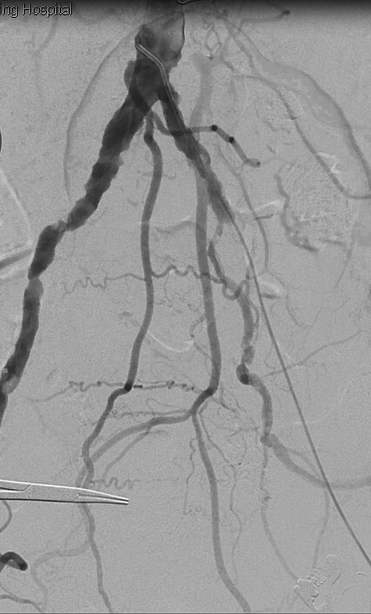

2. 沿左侧股总动脉切口,找出血管真腔,导丝配合椎动脉导管成功通过左侧髂动脉闭塞段,建立通路,造影如下:

3. 于左侧股浅动脉引出导丝,以血管滑线缝合股总动脉以及股深动脉切口,沿导丝引入8F短鞘,导引3.5mm球囊扩张后,未防止充分预扩导致血管破裂,先行植入支架(依次于髂外植入8*100mm覆膜支架、髂总动脉植入8*80mm支架、髂外动脉腹膜支架内嵌入8*60mm支架),导引8mm球囊进行后扩张,扩张后支架形态如下: